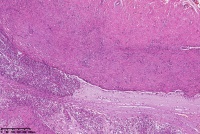

符合甲状舌管囊肿?

性别

男

年龄

39岁

临床诊断

颈部包块

一般病史

标本名称

大体所见